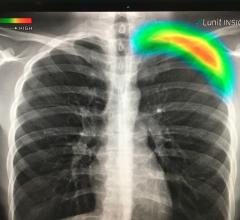

News | Artificial Intelligence

February 4, 2020 — Since January 2020, the Coronavirus (2019-nCoV) outbreak at Wuhan, China, has attracted a great deal…